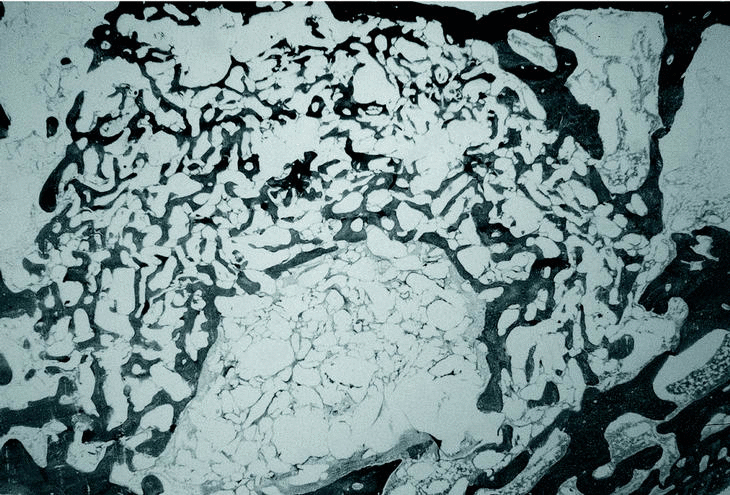

En los grupos PLA 80/20 (30.000) (fig. 1), PLA 80/20 (60.000) (fig. 2) y PLA 50/50 (60000) (fig. 3) se observó escasa neoformación ósea con abundante material polimérico con pocos signos de reabsorción a las 12 semanas y tejido fibrótico intraimplante y periimplante entre los gránulos de polímero, con presencia de células gigantes multinucleadas.

Figura 2. Grupo PLA 80/20 60.000 a las 12 semanas. Escasa neoformación ósea y abundantes gránulos de polímero (Tric.,x10).